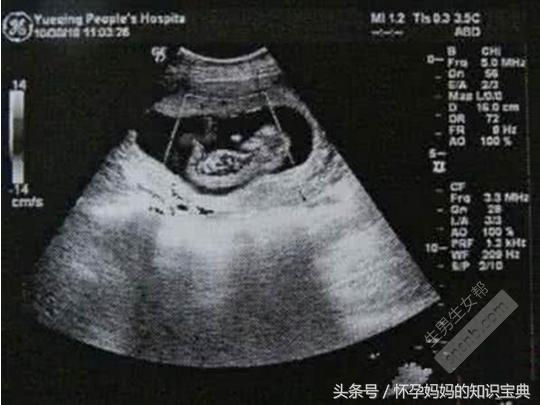

如圖所示是超音波圖片;其中資料顯示:

雙頂徑6.6cm,腹圍6.7*7.0cm,股骨徑長4.8cm,胎心率148次/分,節律整齊。

脊柱呈現雙排“串珠樣”,排列整齊,彎曲度正常,胎盤位於子宮前壁,厚約4.4cm。

這是6個月的超音波單,懷的可愛的女寶寶。